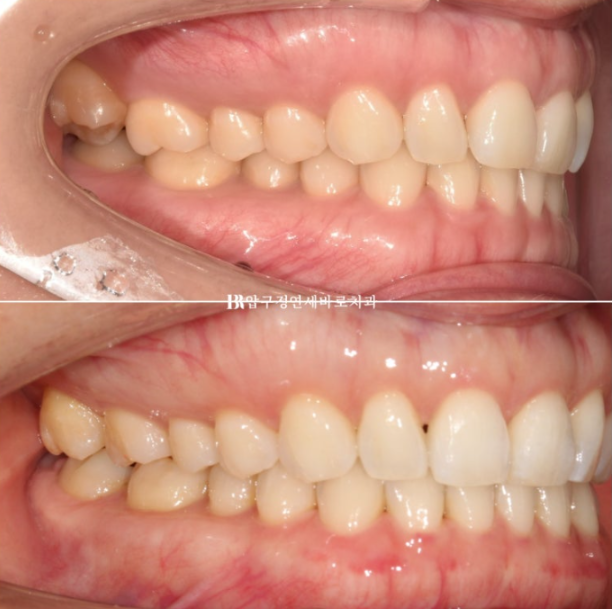

오른쪽 맨 뒤 큰 어금니의 가위교합이 보이고 왼쪽은 송곳니와 앞니 사이 벌어진 공간이 보입니다.

23.07~24.05

악궁 모양과 배열이 잘 잡혔고 재제작때 미니스크류 뺀 자리는 잘 아물어서 흔적이 없습니다.

흉터가 작게 남는 경우도 있지만 흉터가 남지 않는 경우가 많습니다.